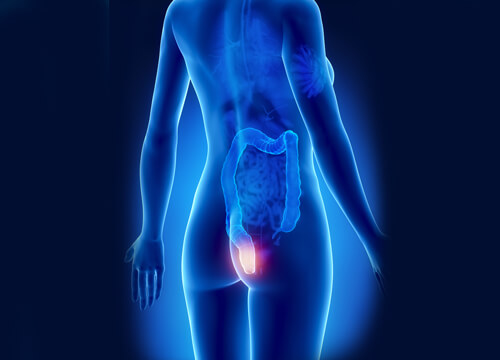

치질은 흔히 발생하는 혈액순환 질환으로 보통 직장이나 항문 아래쪽 정맥에 염증이 생기거나 붓는 증상을 말하며 통증, 자극, 출혈을 일으킨다.

치질은 임산부나 지나치게 힘을 주어 변을 보려는 사람에게 흔히 나타나며 발병 원인은 다양하다. 치질이 유발하는 문제와 위험 요소 때문에 치질을 제때 발견하는 일은 아주 중요하므로 그 방법을 알아보도록 하겠다.